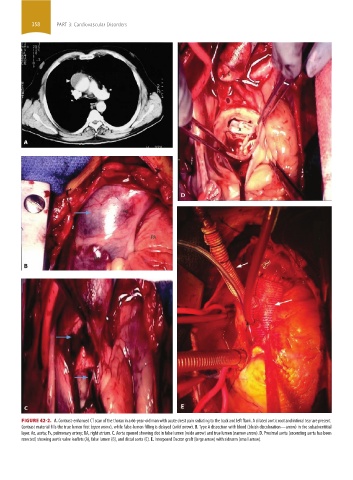

FIGURE 42-2. A. Contrast-enhanced CT scan of the thorax in a 66-year-old man with acute chest pain radiating to the back and left flank. A dilated aortic root and intimal tear are present.

Contrast material fills the true lumen first (open arrow), while false-lumen filling is delayed (solid arrow). B. Type A dissection with blood (bluish discoloration—arrow) in the subadventitial

layer. Ao, aorta; Pa, pulmonary artery; RA, right atrium. C. Aorta opened showing clot in false lumen (wide arrow) and true lumen (narrow arrow). D. Proximal aorta (ascending aorta has been

resected) showing aortic valve leaflets (A), false lumen (B), and distal aorta (C). E. Interposed Dacron graft (large arrow) with sidearm (small arrow).